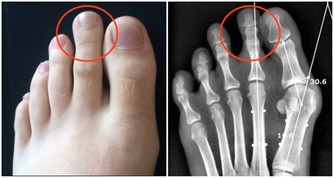

4、指甲不正常——指甲上出現凹凸不平的豎紋,有些人指甲還發黃;